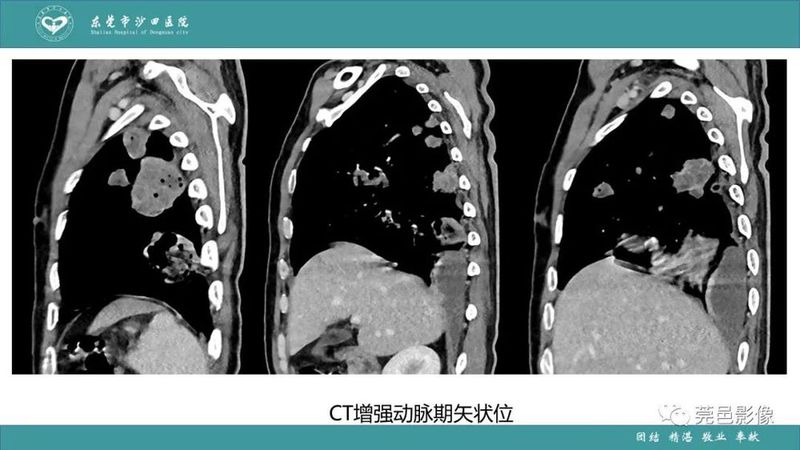

「肺炎克雷伯杆菌肺炎」影像学诊断+鉴别诊断